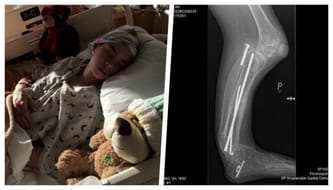

Po wykonanym zdjęciu RTG, kolano jest w fatalnym stanie i, mówiąc w prostym języku, zaczęło się cofać. Alan w tej chwili ma już dolegliwości bólowe przy zginaniu i prostowaniu nogi. Jeśli operacji nie zrobimy w najbliższym czasie, jego kolano cofnie się na tyle, że Alan wyląduje na wózku.

Jest to bardzo skomplikowana operacja, której nie chcą się podejmować lekarze w Polsce. Zresztą, żeby taka operacja miała sens i szanse na powodzenie, musi ją wykonać ktoś, kto ma ogromne doświadczenie z tego typu wadami, a dr Paley ma największe na świecie. Niestety, taki zabieg to ogromny wydatek...